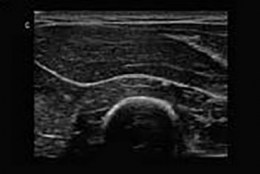

Кардіологія • Ветеринарні УЗД • Радіологія • Реанімація • Хірургія • Ендоскопія • Лабораторія • Реагенти • Діагностика: (ЛОР обладнання / Офтальмологія / Дерматоскопія) • Стоматологія • Дезінфекція • Тваринництво • Зоотовари • Меблі • Різне